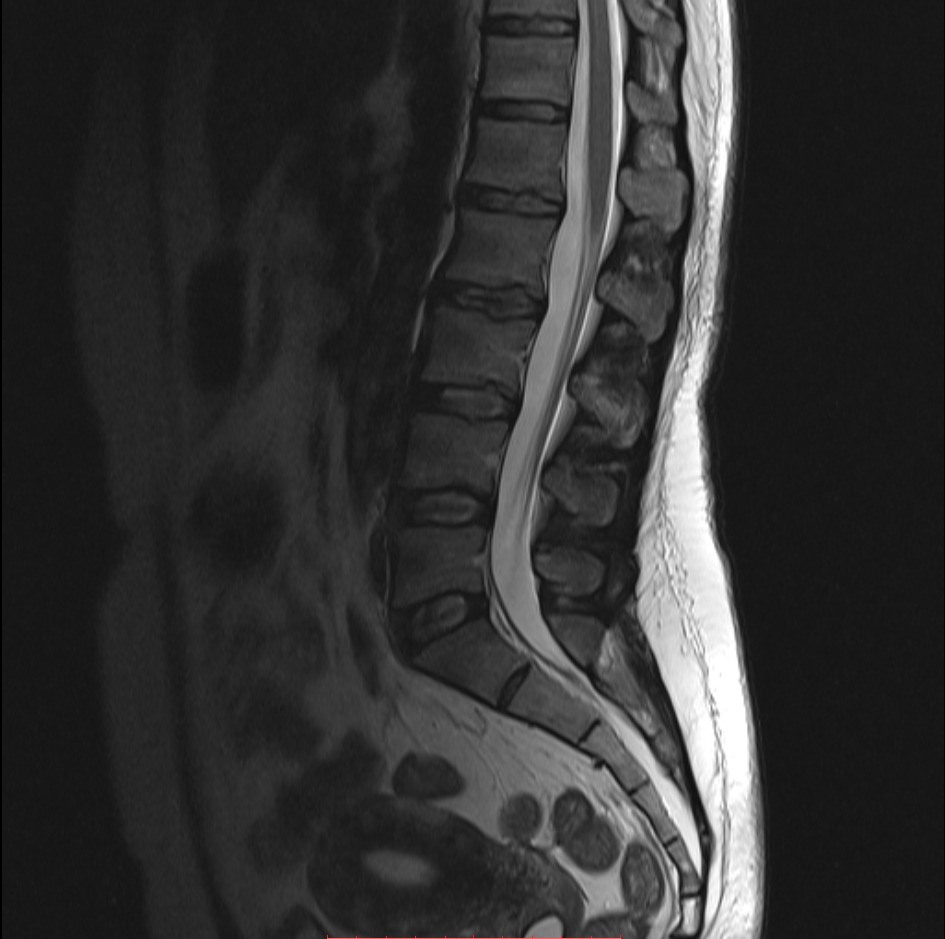

МРТ пояснично-крестцового отдела позвоночника: что показывает, как проводиться и кому противопоказано

МРТ пояснично-крестцового отдела позвоночника